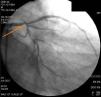

Invasive coronary angiography confirmed significant coronary artery disease (Figure 3) and the patient was referred for coronary artery bypass grafting. The authors did not have access to the initial coronary angiography since this was performed in a different institution, and at referral the patient was in possession of clinical information only, together with the request for cardiac CT angiography.